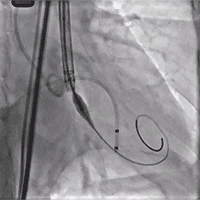

术中影像

球囊预扩

定位胶囊腔